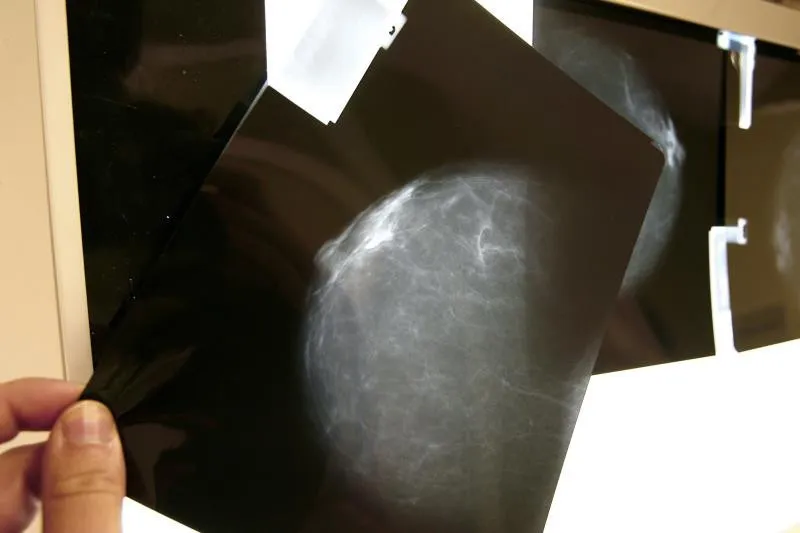

ESPAÑA.- Investigadores del International Breast Cancer Center, ubicado en Barcelona (noreste), han liderado un ensayo clínico que concluye que la prueba de imagen PET-TAC podría identificar alrededor de un 40 % de pacientes con cáncer de mama HER2-positivo localizado que podrían prescindir del tratamiento con quimioterapia.

Todas las pacientes se sometieron a una prueba de imagen con PET-TAC tras dos ciclos de tratamiento para observar la respuesta tumoral.

El resultado del PET-TAC y la respuesta patológica determinó el tratamiento que seguir en las pacientes incluidas en el grupo B del estudio.

El doctor Cortés ha indicado que "los resultados iniciales del ensayo clínico PHERGain demuestran que la evaluación temprana de la respuesta al tratamiento preoperatorio exclusivo con un doble bloqueo del receptor HER2 con trastuzumab y pertuzumab, mediante el uso del PET-TAC, es capaz de identificar aproximadamente a un 40 % de pacientes que alcanzan una respuesta completa patológica sin necesidad de usar quimioterapia".